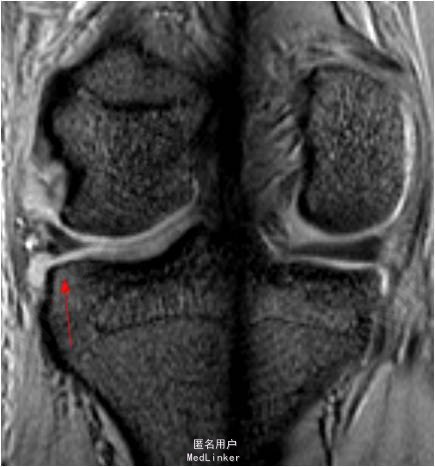

患者男,20岁,因”扭伤后右膝关节疼痛3周”入院。患者受伤时自觉右膝髌骨往外脱位,后自行复位。

查体:右膝关节无肿胀,浮髌征(-),髌骨恐惧试验(+),研磨试验(+),ADT(-),lachman征(-),麦氏征(+),PDT(-),侧方应力试验(-),关节活动度0-135度,股四头肌无明显萎缩,肌力正常;肢端血运、感觉、活动正常。MR提示:1.右膝髌骨脱位:MPFL损伤;2.右膝关节半月板损伤

诊断:1.右膝髌骨脱位:MPFL损伤 2.右膝关节半月板损伤 行右膝关节镜检,半月板修补,关节镜监视下MPFL探查+修补术